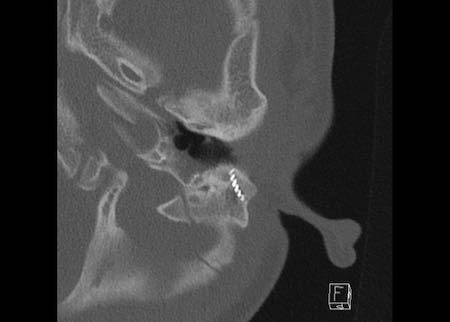

Bên trái là hình ảnh của một bé trai 2 tuổi với teo ống tai ngoài xương hai bên.

Xương búa và xương đe hợp nhất (mũi tên).

Ốc tai bình thường.